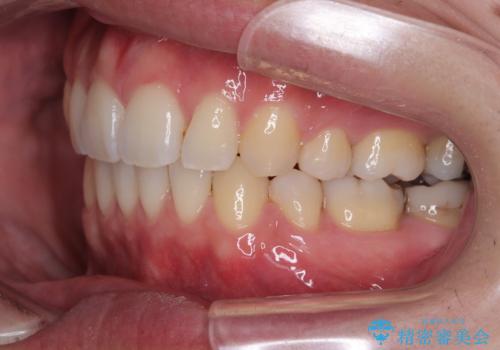

左上はアンカースクリューを併用することでスムーズに抜歯スペースを閉じることができました。

口元の突出感もなくなり満足されました。